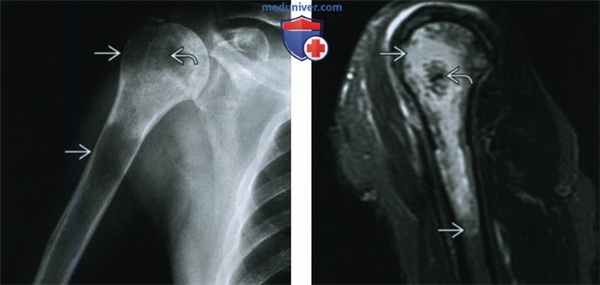

(Слева) Рентгенография в ПЗ проекции: светлоклеточная хондросаркома, представленная смешанным литически-склеротическим очагом, распространяющимся от головки плечевой кости в метадиафизарную зону. В проксимальной части виден слабовыраженный хрящевой матрикс.

(Справа) МРТ, сагиттальная проекция, режим Т2 с подавлением сигнала от жира: крупный интрамедуллярный очаг, поражающий головку и проксимальный отдел диафиза плечевой кости, характеризуется гиперинтенсивным сигналом по отношению к скелетной мышце. Наличие низкоинтенсивного хрящевого матрикса является признаком хондросаркомы. Эпифизарное происхождение опухоли предполагает ее светлоклеточный вариант.